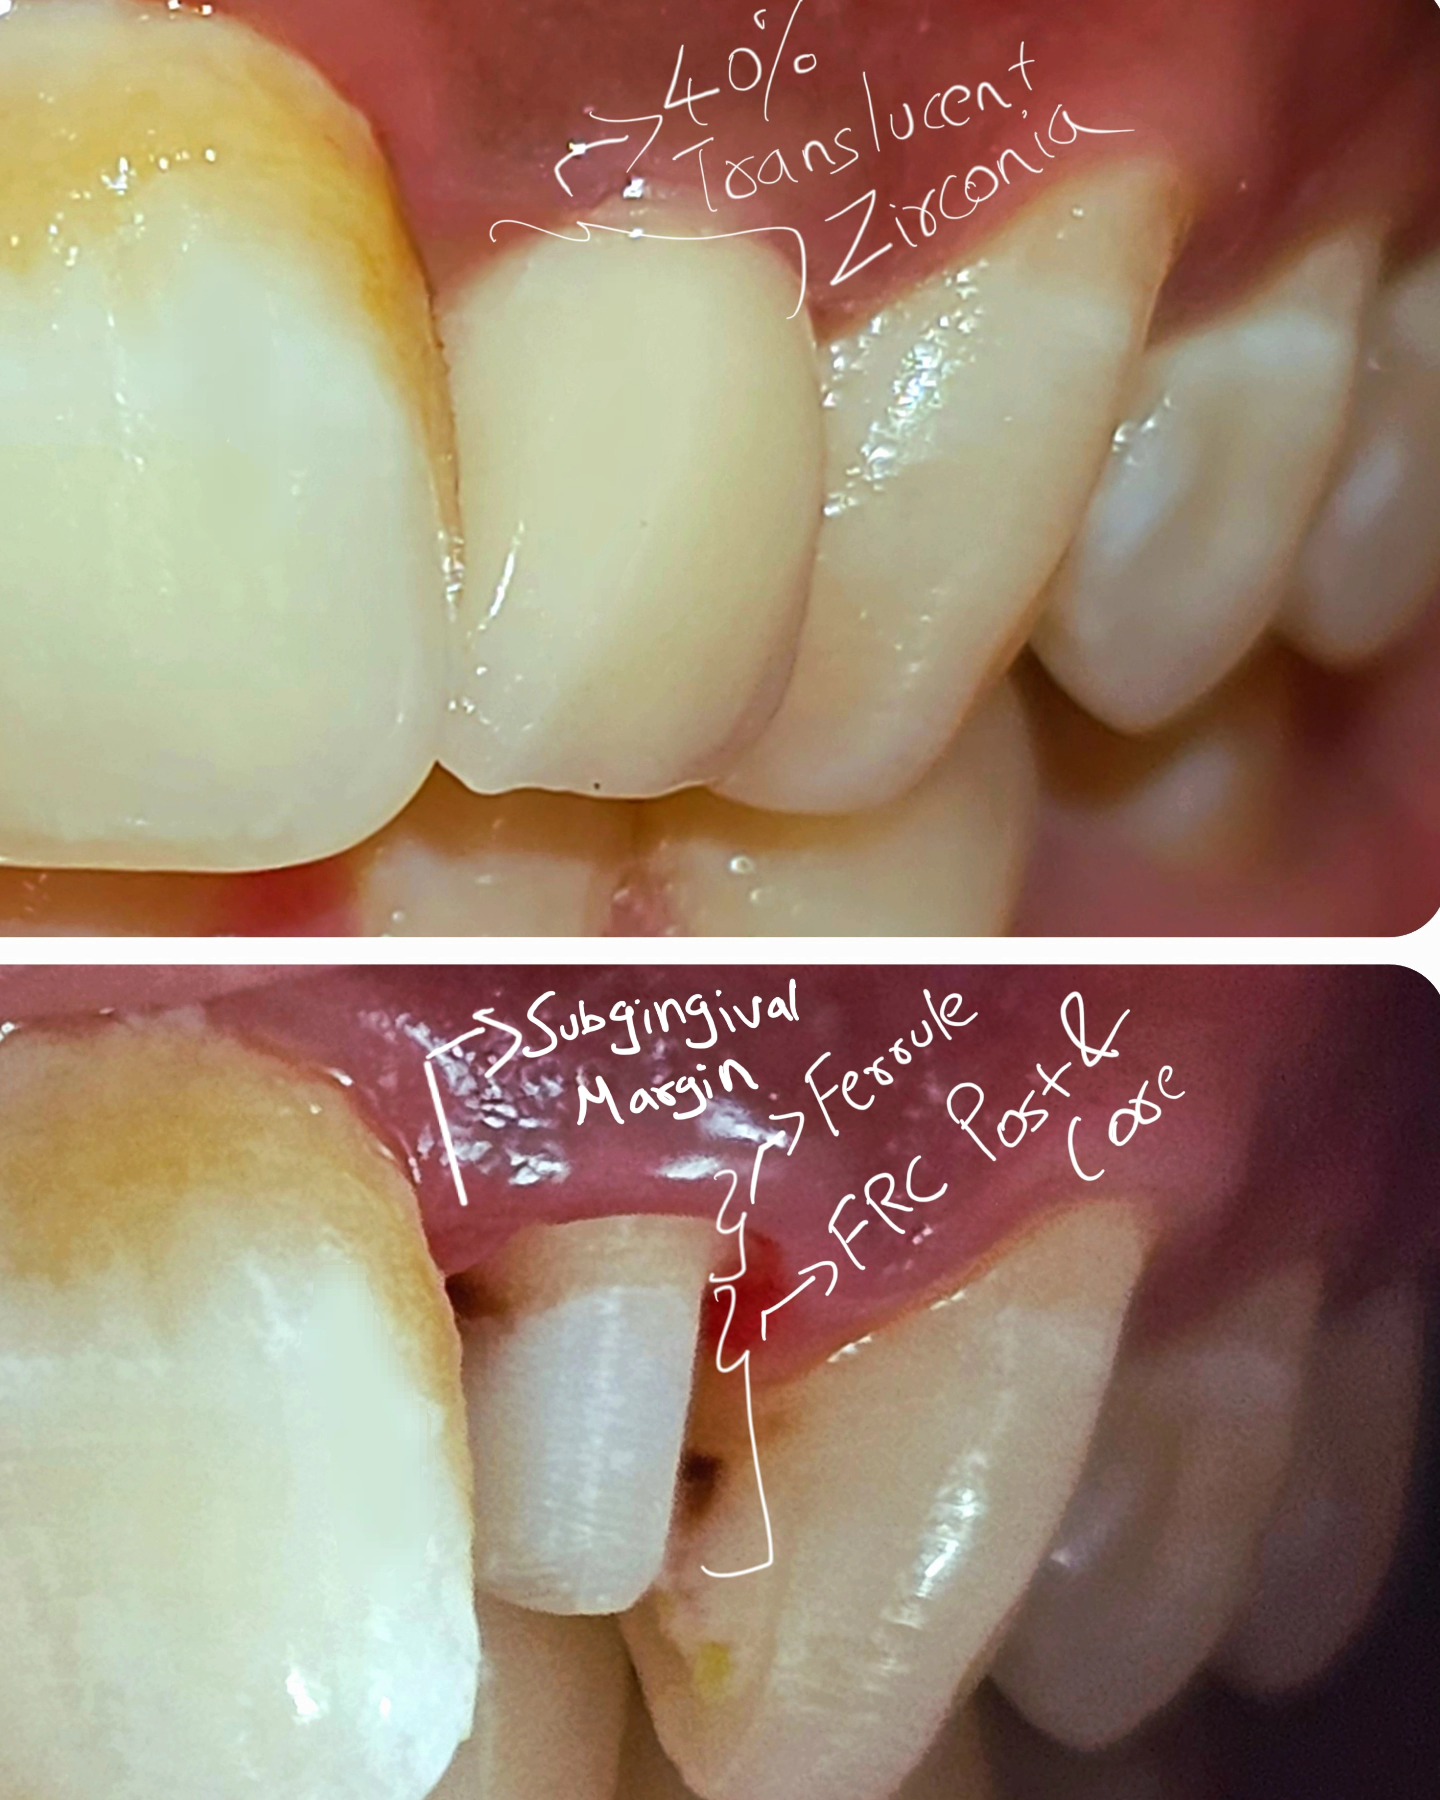

At our dental clinic, we understand the importance of maintaining healthy and strong teeth. Our Post and Core Build Up treatment is designed to do just that, by increasing the strength and durability of root canal treated teeth and preventing future fractures. Our team of experienced dentists use the latest techniques and materials to provide a reliable and long-lasting solution.